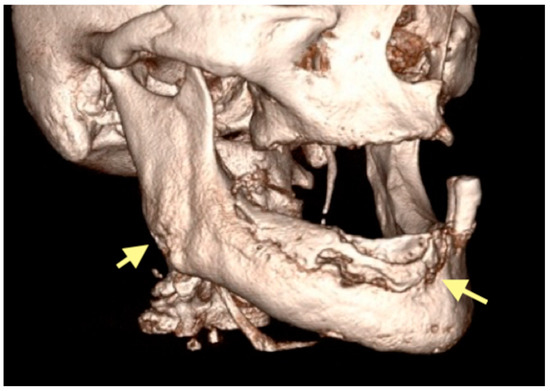

The third patient was a 75-year-old female with osteonecrosis of the mandible and maxilla in the fourth and in the second quadrant (see Figure 7, Figure 8 and Figure 9). The patient had third-stage jaw osteonecrosis. In 2023, the patient was diagnosed with osteonecrosis of the upper and lower jaw caused by antiresorptive therapy (until August 2021, the patient regularly used Zolendronic acid; then, this drug was replaced by the RANKL inhibitor Denosumab). The treatment was periodically complicated by submandibular and submental abscesses. In addition, due to the progression of the underlying disease, constant courses in chemotherapy were administered. The patient underwent three operations, which included sequestrectomy of the jaw with simultaneous use of A-PRF, antrotomy with revision of the maxillary sinus, closure of the oroantral communication, and opening and revision of abscesses of the soft tissues (see Figure 10 and Figure 11)

Figure 7.

CT of the head and facial bones (16 December 2024).

Figure 8.

Figure 9.